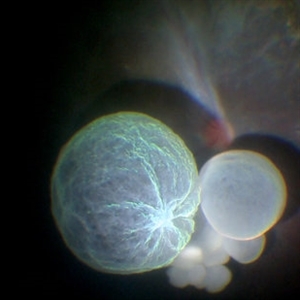

Intraocular Multiple Cysticercus

Intraoperative fundus picture of right eye of a 18-year-old boy with complaints of DOV for the past 2 months. There were 12 intravitreal cysts in total with vitritis sclerosis retinal vessels and TRD. To note here, the largest cyst has a flimsy wall and no scolex (possibly ruptured) and the rest of the smaller cysts have a scolex and a taut wall.

Photographer: Vishal Agrawal MD,FRCS

Imaging device: SONY PMW-10 MD HD

Condition/keywords: cysticercosis, scolex